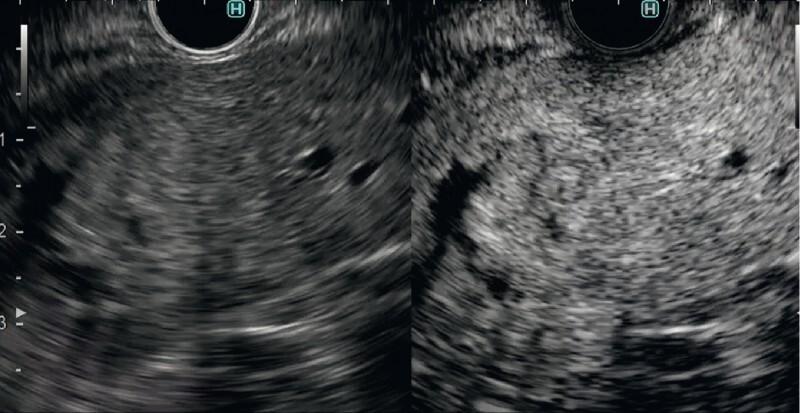

Diagnosis of an intraductal papillary neoplasm of the bile duct with fibrovascular stalks using detective flow imaging.

Endoscopy. 2023 Dec;55(S 01):E1012-E1014. doi: 10.1055/a-2134-9350. Epub 2023 Aug 30.